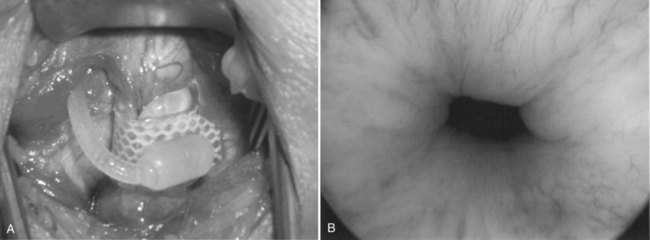

After incising the skin, Colles fascia, and bulbospongiosus muscle, Buck fascia is incised as it reflects off the bulbar urethra onto the diverging corporeal bodies (Fig. 79–4C). A 2-cm wide tunnel is created under direct vision using sharp dissection, dorsal to Buck fascia over the roof of the urethra. A right-angle clamp is then passed through this tunnel (Fig. 79–4D). Blunt spreading dissection is discouraged in this area, because it risks injury to the urethra, especially in reoperative cases. The circumference of the urethra is measured around the corpus spongiosum to guide selection of cuff size, most commonly 4.0 or 4.5 cm. The urethral catheter should be removed prior to measurement. Although some authors advocate selecting a cuff size 0.5 to 1 cm smaller than the measured circumference of the urethra to compensate for postoperative subcuff atrophy of the spongiosum, the best test of cuff fit is the visual and endoscopic appearance after it has been placed around the urethra (Fig. 79–5A and B). If the cuff size is obviously incorrect, the next appropriate size should be selected. The tubing from the AUS cuff is then passed through the overlying bulbospongiosus muscle into the deep perineal space beneath Colles fascia.

Figure 79–5 Appropriate appearance of cuff. A, Perineal placement encircling the bulbar urethra. B, Endoscopic appearance with cuff activated.